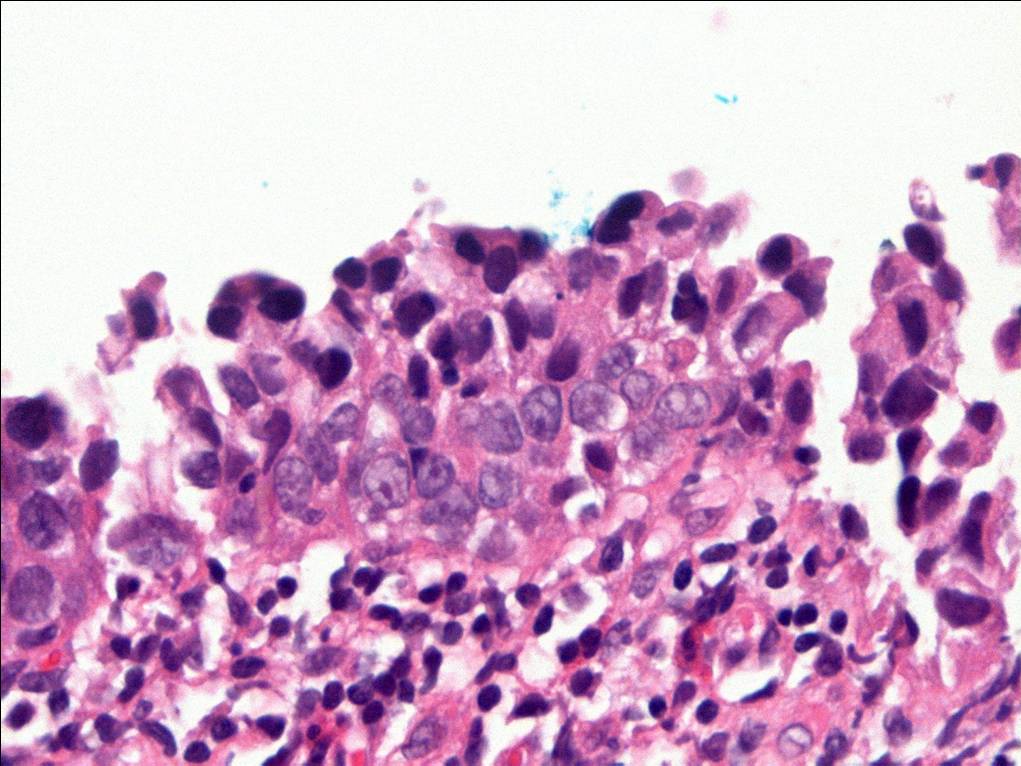

Consensus grade: Carcinoma in situ (CIS)

Some of the atypical urothelial cells present have high nuclear:cytoplasmic ratio raising the possibility of at least some element of so-called 'small cell' urohtlelial CIS (not meant to imply neuroendocrine differentiation). |

Case description (by case creator):

The degree of cytologic atypia and loss of polarity is disproportionate to the inflammation present in the lamina propria and the degree of atypia is greater than would be acceptable for reactive atypia.